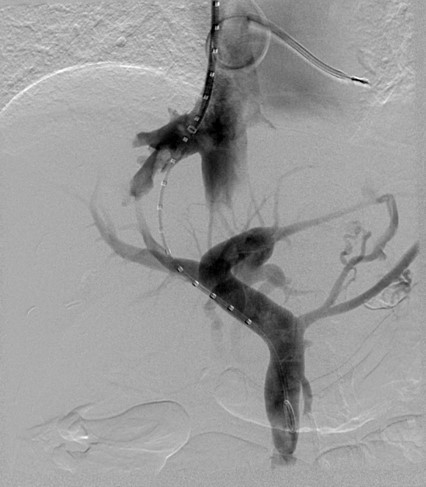

Which is the most typical first-line approach to TIPS?

R hepatic vein –> R portal vein

best intervention for budd-chiari

TIPS

type of stent used in TIPS

Viatorr stent

it is both covered and uncovered